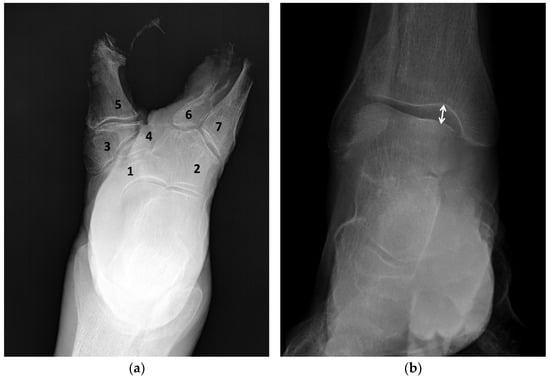

Background: Congenital split foot/hand is a rare limb anomaly. Although various surgical techniques have been described, detailed gross anatomical studies of soft tissue adaptation, particularly in the foot, are extremely rare. This study presents a detailed anatomical description of a case of severe

Background: Congenital split foot/hand is a rare limb anomaly. Although various surgical techniques have been described, detailed gross anatomical studies of soft tissue adaptation, particularly in the foot, are extremely rare. This study presents a detailed anatomical description of a case of severe bilateral split foot. Methods: A comprehensive dissection was performed on the lower limb of a 64-year-old male donor with bilateral split foot/hand. Results: Radiographic evaluation classified the deformity as Blauth type IV, characterized by the absence of the lateral cuneiform bone and severe hypoplasia/aplasia of the second and third metatarsals. Significant changes were revealed in the musculotendinous apparatus. The key finding was a unique tendon loop passing through the central cleft, formed by the tendon of the extensor digitorum longus and connecting with the tendons of the flexor digitorum longus and flexor hallucis longus. Conclusions: This study presents the first detailed macroscopic anatomical description of split foot, demonstrating that this congenital anomaly involves complex, structured tendon and muscle adaptations that extend beyond skeletal deficiencies alone. The discovery of a persistent tendon loop—previously reported only once in split hand—indicates asynchronous development of skeletal and soft tissue structures. These findings should be taken into account for surgical planning, emphasizing the need to identify and manage such abnormal soft tissue structures during reconstructive procedures.